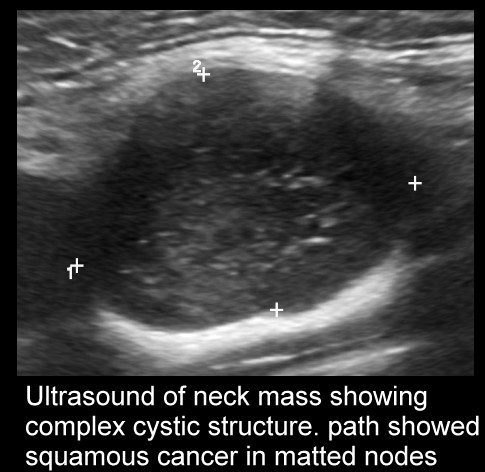

Ultrasound scan of neck mass